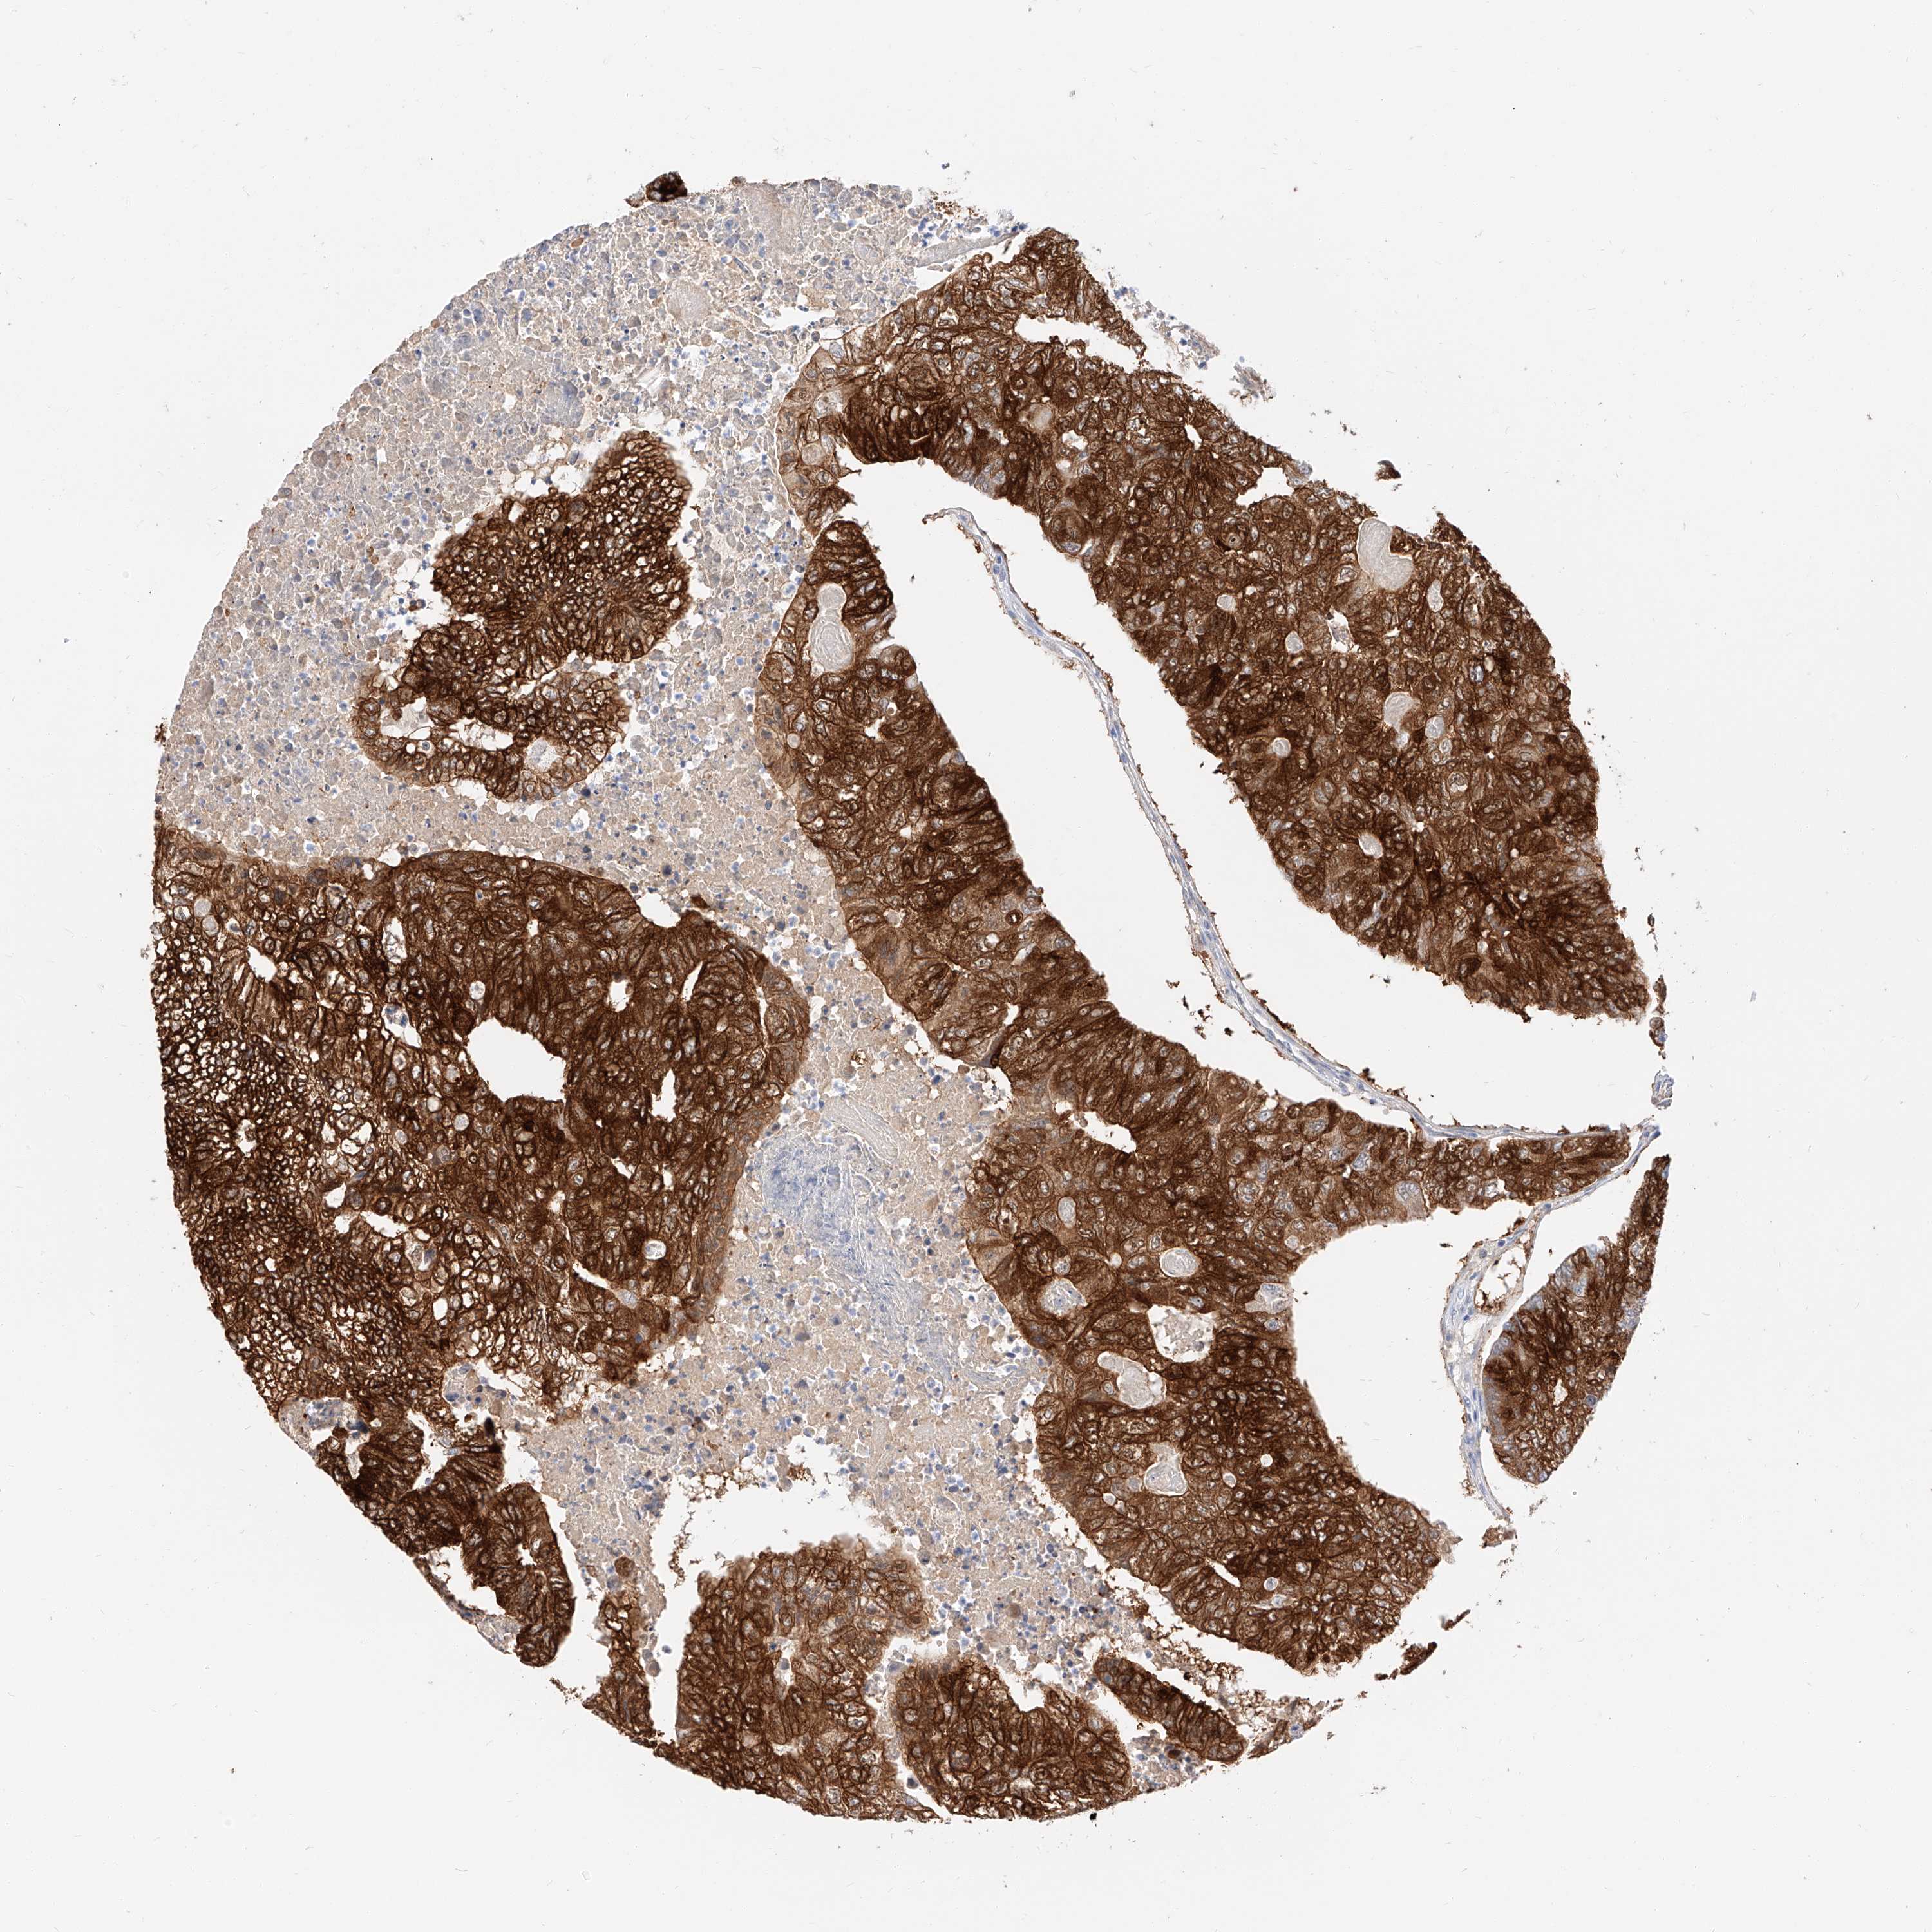

CANCER COLORECTAL CANCER Show tissue menu

ANTIBODIES

AND

VALIDATION